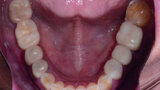

Restoring function and aesthetics with monolithic zirconia restorations